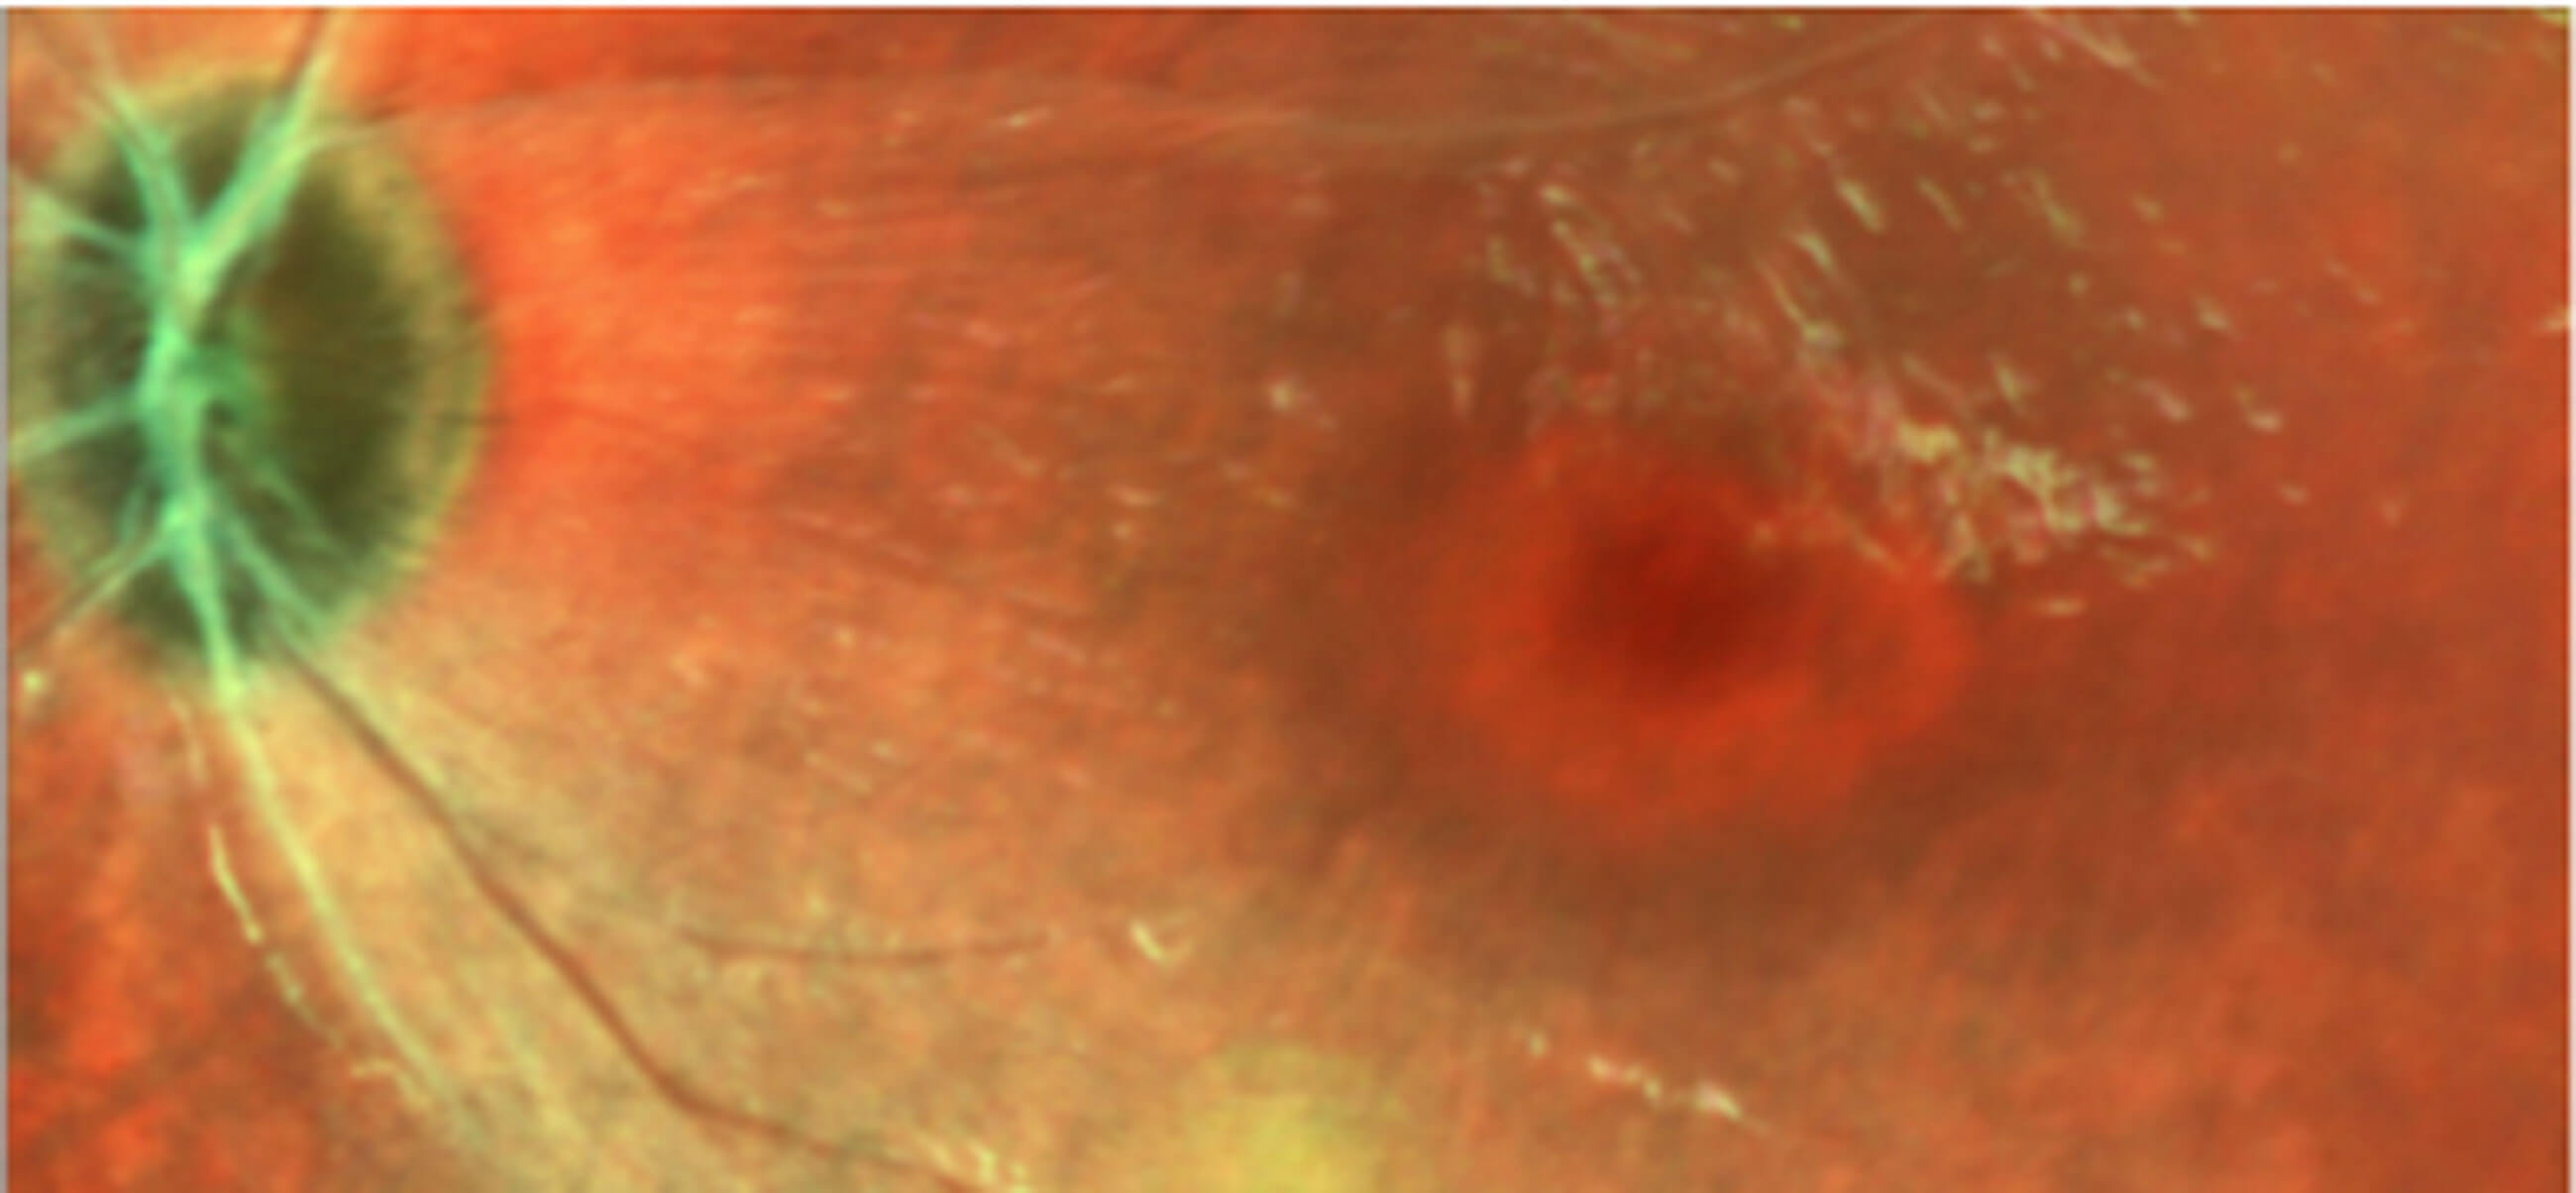

Figures 2 & 3: Cropped Spectralis OCT and MultiColor images showing parafoveal

loss of ellipsoid and bull’s-eye maculopathy in patient with CLN2 disease.